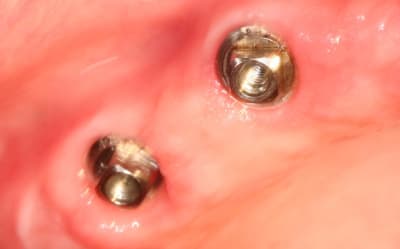

Pour ceux que ca interessent, et parce qu on a m a demandé des cas supplémentaires dans le sujet 23 implants rehabilitation totale, voici un autre cas d implantation immédiate avec la technique minimalement invasive et condensation grace aux forets.

Le patient a reçu un traitement il y a dix ans dans le maxillaire et dans le 4eme quadrant.Comme on peut le voir j´ai du extraire quelques dents au maxillaire: 35 37 et 45.

Le septum de la 37 a été foré avec un foret conique 3 faces.

J ai planté à 60 Ncm sans fracturer le septum.Juste après l opération , les prep caps en zircon ont été cémenté.La restauration définitive 34 jusqu` à 37 été fixé 2 semaines après l implantation avec implantlink (detax). Après un an, le bridge a été retiré facilement pour voir l´état de la gencive et faire une radio de contrôle.On la re ossifiction est satisfaisante et que la gencive "aime" le zircon.

Le bridge a ensuite été recémenté sans correction nécessaire du bridge.